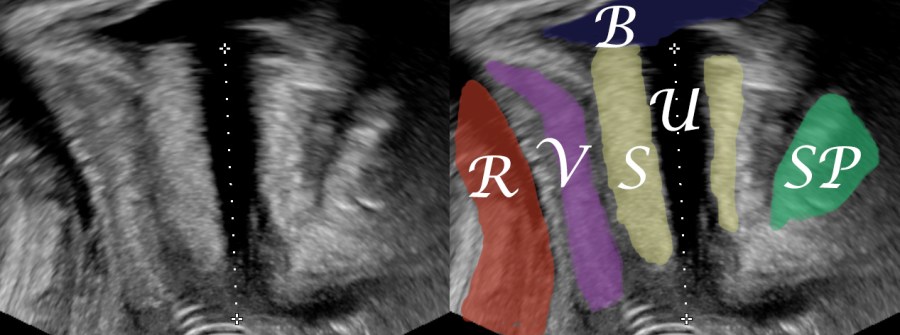

An 80-year-old female patient presents with persisting overactive bladder symptoms. After careful ultrasound examination, a unilocular cystic mass with a single urethral connecting tract containing a calculus was identified as an urethral diverticulum.

One way to provide a description of a diverticulum is the classification L/N/S/C3 suggested by Leach et. al.:

Location (proximal, mid, distal) / Number of diverticula / Size (diamensions in cm) / Configuration (single, multiloculated or saddle-shaped) / Communication site (proximal / mid / distal) / Continence

Classification by Leach et. al:

L (distal) / N (1)/ S (1cm) / C (single) / C (distal) / C (overactive bladder)